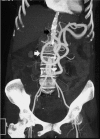

CT abdominal angiography maximum-intensity projection (MIP) image showing atherosclerotic occlusive aortoiliac disease (black arrow) with Arc of Riolan (white arrow) connecting SMA and IMA.